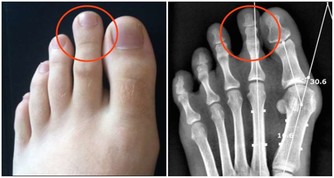

下肢水腫或外陰腫大:

腫瘤長到一定大小后,會壓迫盆腔,使血流不暢,進而表現為外陰腫大和下肢水腫的現象。